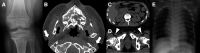

Results: Using these strategies, 8/31 cases were solved, increasing the overall diagnostic yield of this cohort from 10/41 (24.4%) to 18/41 (43.9%). Exemplar cases include a patient with cystic fibrosis harbouring a novel exonic LINE1 insertion in CFTR and a patient with generalised arterial calcification of infancy with complex interlinked duplications involving exons 2-6 of ENPP1. Although ambiguous by short-read WGS, the ENPP1 variant structure was resolved using optical genome mapping and RNA analysis.